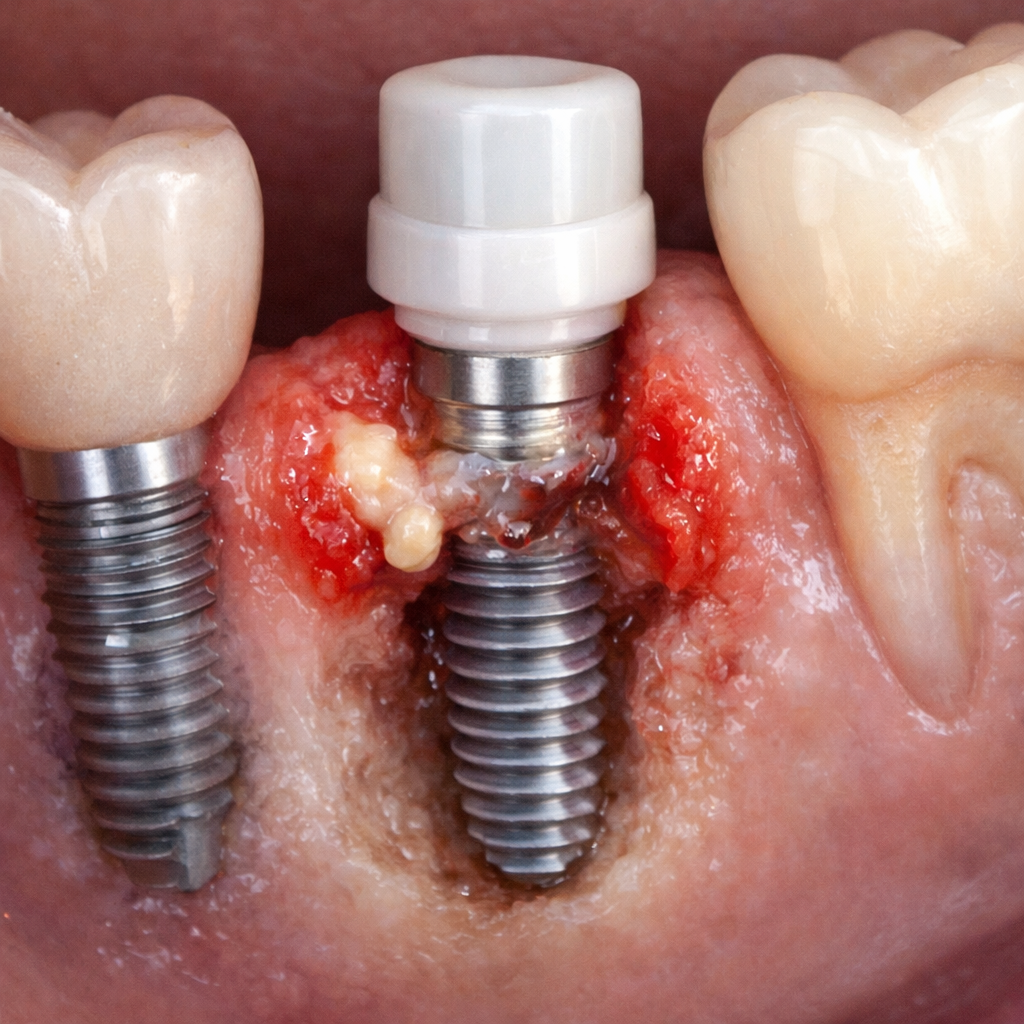

La periimplantitis es una enfermedad inflamatoria que afecta a los tejidos periimplantarios, caracterizada por inflamación de la mucosa y pérdida progresiva de hueso alrededor del implante.

- Sangrado al sondaje

- Supuración

- Aumento de la profundidad de sondaje

- Pérdida ósea observable en radiografías